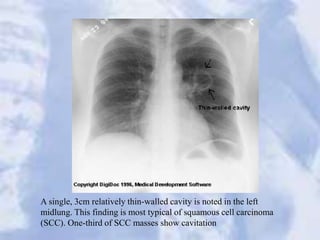

A single, 3cm relatively thin-walled cavity is noted in the left

midlung. This finding is most typical of squamous cell carcinoma

(SCC). One-third of SCC masses show cavitation

A single, 3cmrelatively thin-walled cavity is noted in the left midlung. This finding is most typical of squamous cell carcinoma (SCC). One-third of SCC masses show cavitation